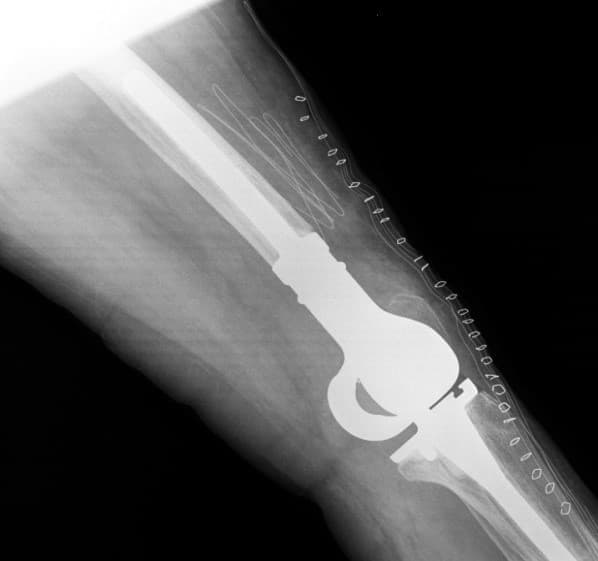

Үе дайрсан ясны анхдагч хавдар, ясны дутмагшлын үед хийгдэх мэс засалimg15Үе дайрсан ясны анхдагч хавдар, ясны дутмагшлын үед хийгдэх мэс засалimg16

Зураг 3. Мэс заслын дараах рентген зураг. Эгц урд, хажуугаас авсан байдал

Өвдөгний үений шөрмөсөн холбоосууд үрэвслийн улмаас бүрэн гэмтсэн Дунд чөмөг - шилбэ ясны 3 зэргийн дутмагшилтай учир дунд чөмөг-өвдөгний хавдрын протез сонгон суулгасан. Энэ дунд чөмөг-өвдөгний хавдрын протезын онцлог нь шилбэ болон дунд чөмөгний хэсэг нь хоорондоо давхар холбогдох нугас буюу hinge system-тэй юм. Hinge system нь үений холбоосын үүргийг гүйцэтгэн – үе хоорондын зайг барих, үений тогтвортой байдлыг хангах зорилготой.